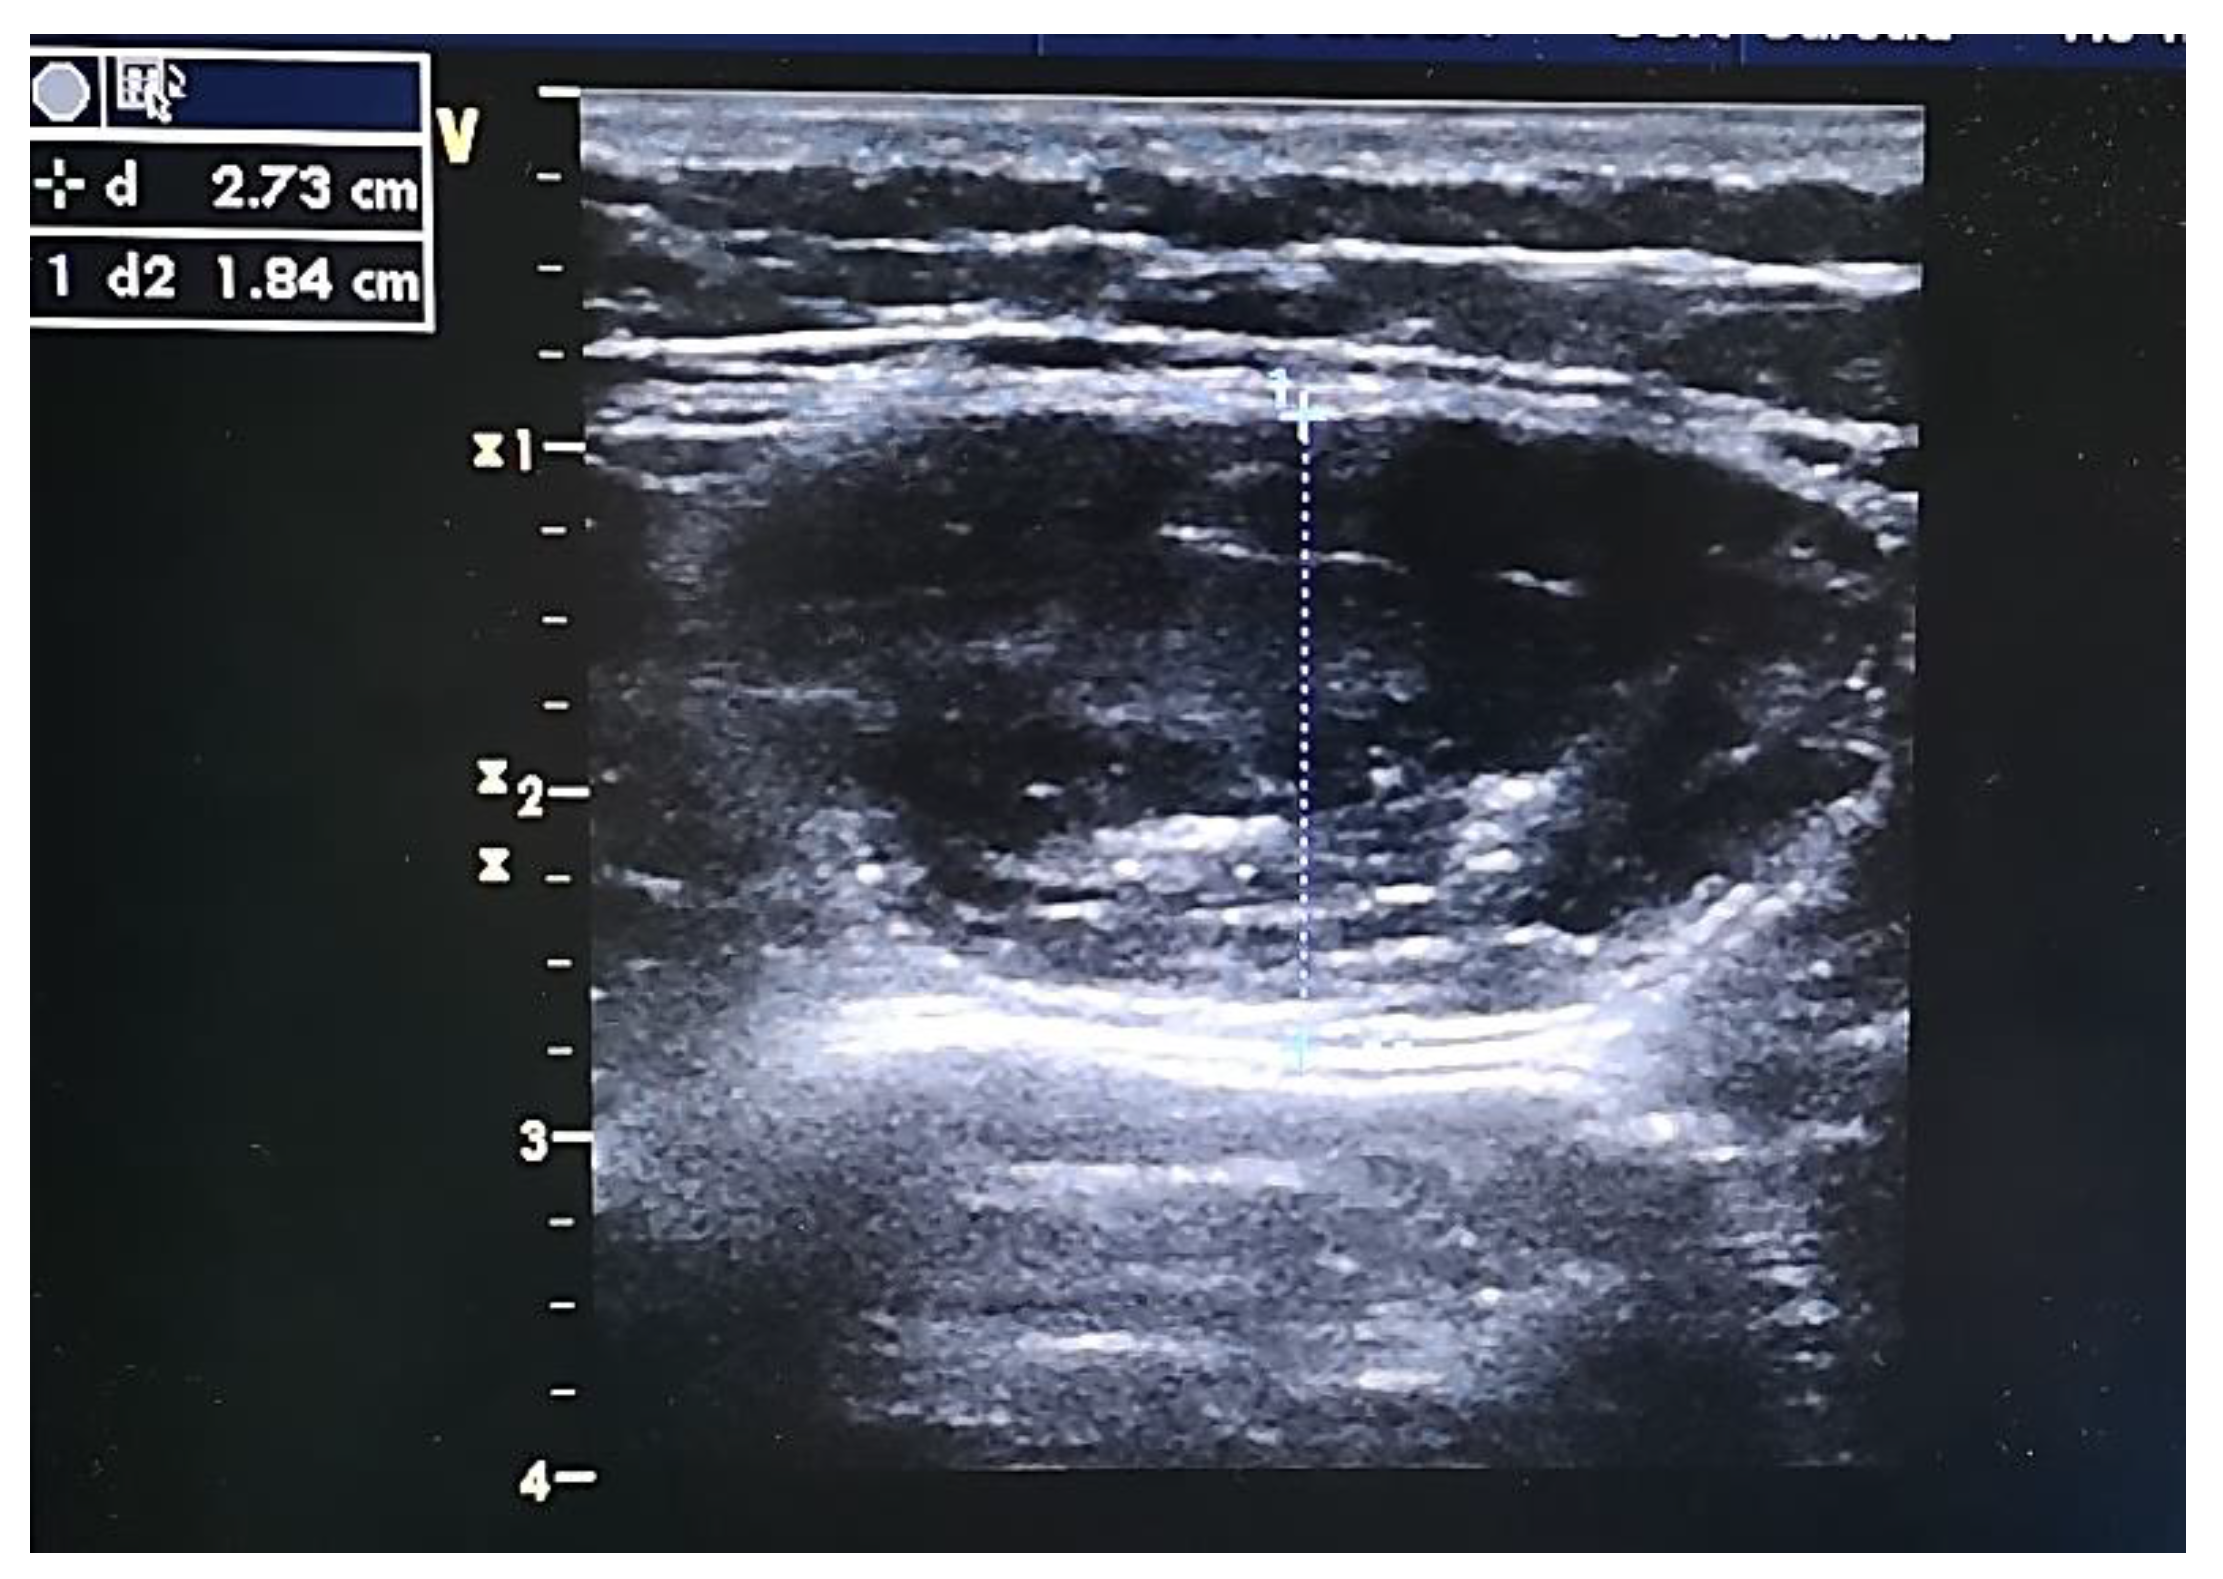

2.8.2. B-Mode US